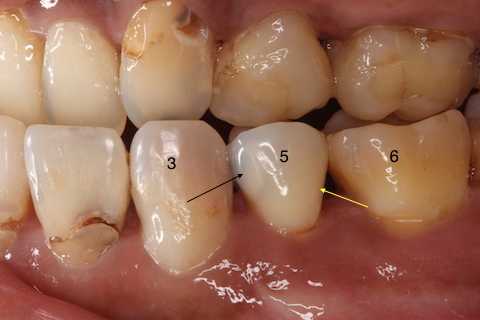

今回の処置は楕円で囲っている左上5番の近心隣接面カリエスだ。

患者は沁みているのは5番ではなくて奥側の6番かもしれないとおっしゃる。

以下は術前の画像だが、5番にも6番にもクラックはあるので、これだけではどちらが沁みているのか特定できない。

5番には術中から気になっていた大きなクラックが認められたので、この部分は裏面の軟化象牙質はエナメル質を壊さないように丁寧に除去してCRで裏打ちし補強を入れた。